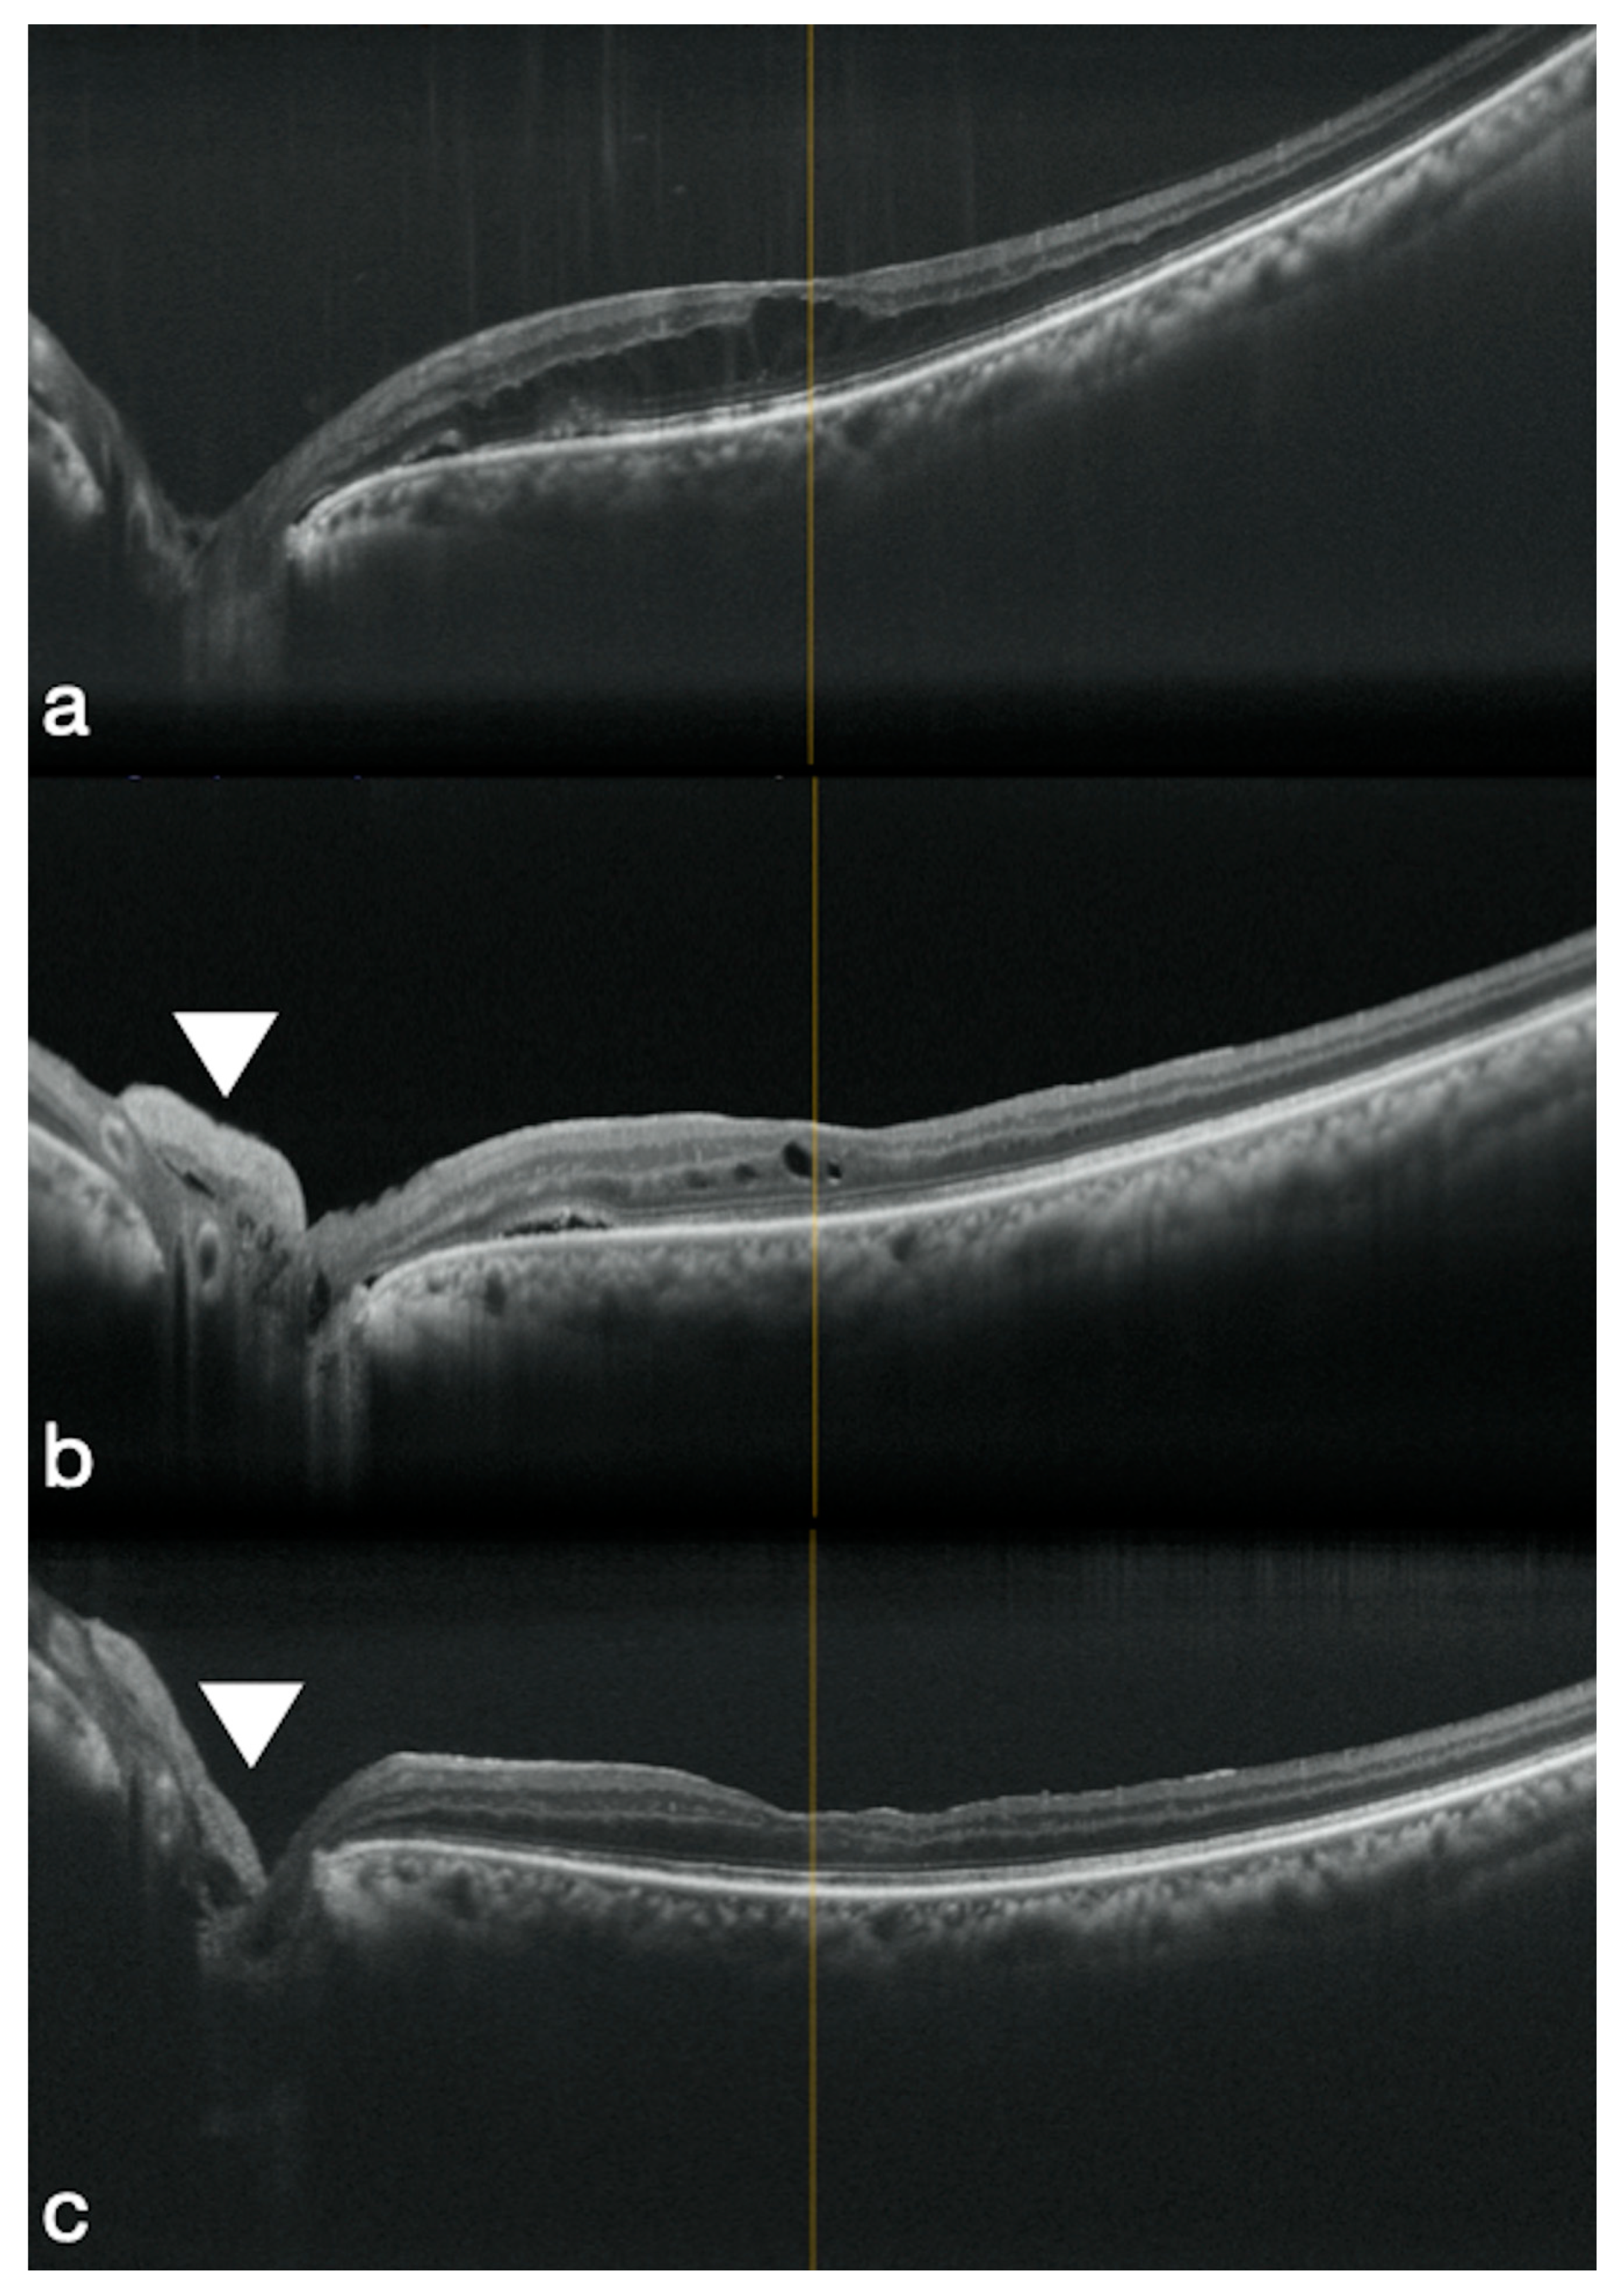

3.2. High Myopic Macular Hole Associated with Retinal Detachment

- Caporossi, T.; De Angelis, L.; Pacini, B.; Tartaro, R.; Finocchio, L.; Barca, F.; Rizzo, S. A human Amniotic Membrane plug to manage high myopic macular hole associated with retinal detachment. Acta Ophthalmol. 2020, 98, e252–e256. [Google Scholar] [CrossRef] [PubMed]

- Caporossi, T.; De Angelis, L.; Pacini, B.; Rizzo, S. Amniotic membrane for retinal detachment due to paravascular retinal breaks over patchy chorioretinal atrophy in pathologic myopia. Eur. J. Ophthalmol. 2020, 30, 392–395. [Google Scholar] [CrossRef] [PubMed]

- Lim, L.S.; Tsai, A.; Wong, D.; Wong, E.; Yeo, I.; Loh, B.K.; Ang, C.L.; Ong, S.G.; Lee, S.Y. Prognostic factor analysis of vitrectomy for retinal detachment associated with myopic macular holes. Ophthalmology 2014, 121, 305–310. [Google Scholar] [CrossRef]

- Coppola, M.; Rabiolo, A.; Cicinelli, M.V.; Querques, G.; Bandello, F. Vitrectomy in high myopia: A narrative review. Int. J. Retin. Vitr. 2017, 3, 37. [Google Scholar] [CrossRef]